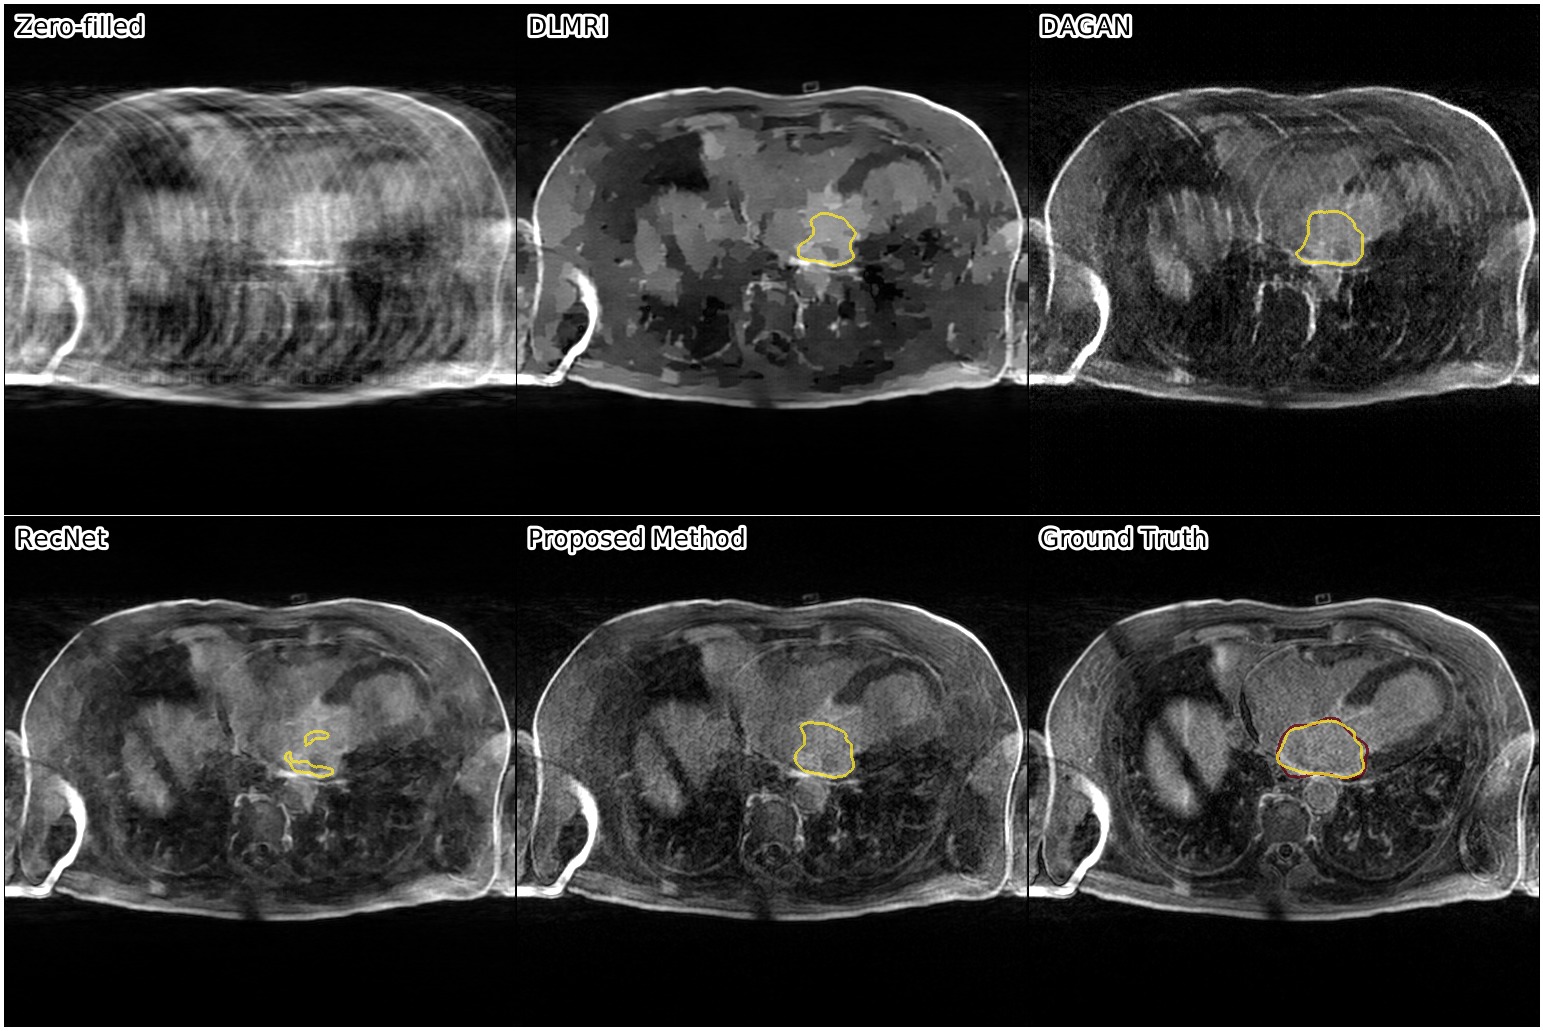

We show the results of our evaluation in Table 1, and a sample reconstruction in Figure 2. RecNet performed best in terms of PSNR, which is expected as its training objective directly corresponds to this metric, but its reconstructions were over-smoothed. DLMRI had the lowest MOS, with its reconstructions showing heavy oil paint artifacts. DAGAN, combining MSE loss with a visual loss function without any further precautions, suffered from low PSNR. While its reconstructions also looked sharp, they were noisy and often displayed aliasing artifacts, which was reflected in a lower MOS compared to our method. Our proposed approach achieved significantly444Significance determined by a two-sided paired Wilcoxon signed-rank test at . higher mean opinion score than all other methods, while still maintaining high PSNR. Reconstructions obtained by our method appeared sharper with better contrast. Moreover, our method achieved the highest SIS close to segmentation performance on the ground truth data, which indicated that the segmented objects were clearly visible in the reconstructed images.

The following images show more samples for 8-fold undersampling. For each of the seven patients of the test set, a random slice showing the left atrium was selected. The contour of the predicted segmentation of left atrium is shown in yellow, the contour of the ground truth segmentation in red.